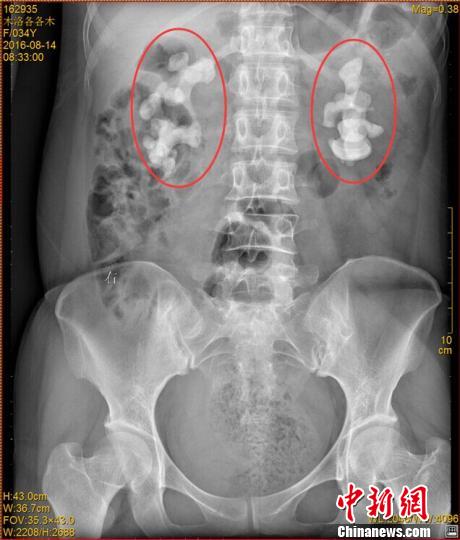

各各木術(shù)前影像圖片,紅圈內(nèi)為巨大腎結(jié)石!$娦馈z

中新網(wǎng)成都11月7日電 (王鵬)記者7日從四川省結(jié)石病醫(yī)院獲悉,該醫(yī)院近日收治了一名罕見腎結(jié)石病人。來自四川涼山的34歲女子各各木,雙腎長出10厘米巨型結(jié)石,腎內(nèi)空間幾乎全被結(jié)石填滿。